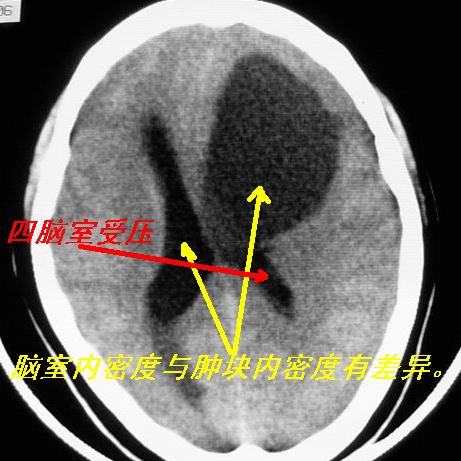

类圆形低密度病灶与脑室内密度明显有差别,考虑:低密度病灶压迫四脑室形成的特殊影像。支持:皮样囊肿。

左额叶见一巨大椭圆形略低、低密度混杂密度肿块,边界清楚,似与侧脑室额角相通,明显占位效应,左侧侧脑室受压变形,右侧侧脑室扩大,中线结构向右明显弧形移位。鞍上池闭塞。

感觉病灶位于侧脑室前角内,而体部受压,病灶形态同前角一致,右侧脑室前角变形并不太严重,病灶呈混杂密度,考虑皮样囊肿或室管膜瘤可能性大一些。